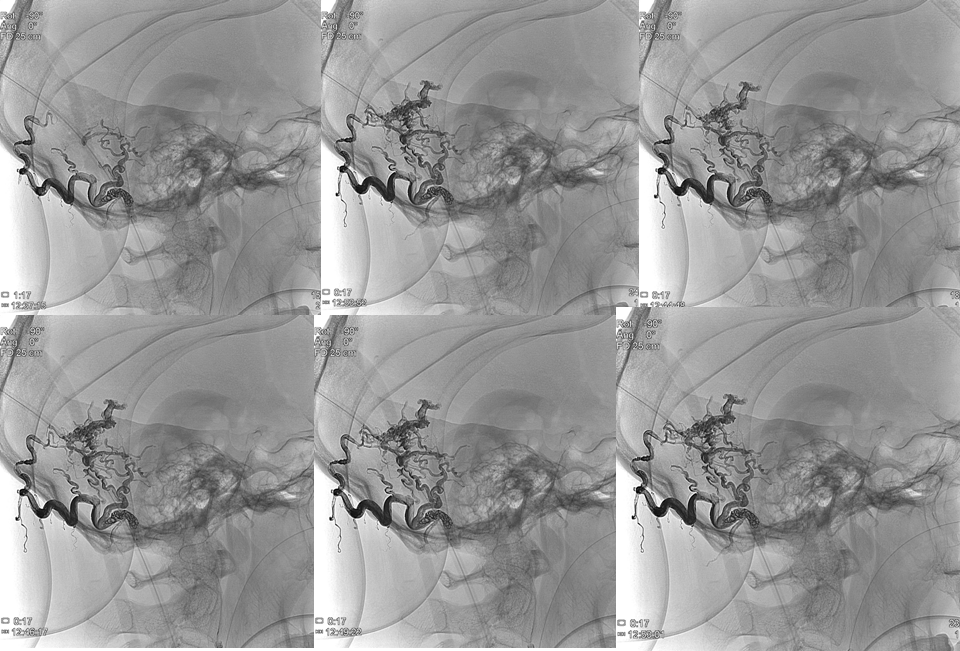

Posteriormente a través del Prowler 10 se procede a crear la oclusión proximal para permitir la olla Express, para lo que empleamos:

- Una cesta inicial con un coil GalaxyG3 12

- Posteriormente se rellena con 3 coils Target Helical Nano (Figura 5)

- En la última fase se procede a inyectar Gluebran que es detenido por los coils y forma un trombo distal a la marca de rotura del apollo.

En series finales de control se observa cierre completo de la fístula (Figura 7)